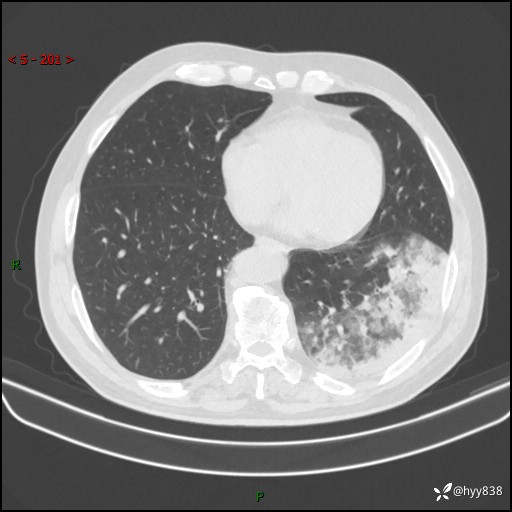

【患者信息】:59岁/男

【主诉】:发热伴咳嗽3天

【现病史及既往史】:患者3天前无明显诱因出现发热,体温最高达38.6℃,伴有咳嗽,干咳为主,感乏力、肌肉酸痛,无明显头晕头痛、鼻塞、流涕、呼吸困难、胸痛、恶心呕吐、腹痛腹泻、尿频尿急等不适,于当地诊所输液治疗3天感症状无好转,仍有间断发热、咳嗽,现为求进一步诊治,于我院门诊就诊,门诊以“发热待查”收入我科进一步诊治。 患者自发病以来,精神、饮食、睡眠欠佳,大小便正常,体力、体重无明显变化。

【检查】:胸部CT平扫